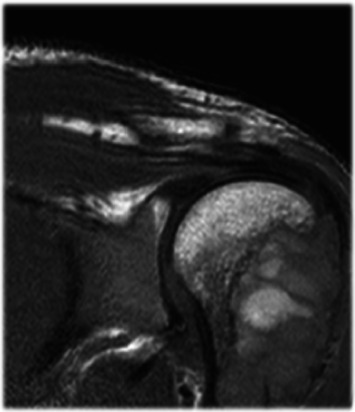

大多数原发性甲状旁腺功能亢进(PHPT)是散发性的,由甲状旁腺瘤引起。遗传性形式可能发生在高达10%的PHPT患者中,更常见于年轻患者。甲状旁腺功能亢进-下颌肿瘤(HPT-JT)综合征的特征是高达95%的患者有PHPT, 25%-50%的患者有颌骨骨化纤维瘤。我们描述的情况下,35岁的男性从孟加拉国转介到我们医院,由于一个巨大的右下颌骨肿胀:一个罕见的非骨化纤维瘤下颌骨被诊断。由于功能性阳痿,左肩磁共振成像(MRI)显示肱骨近端多分叶囊肿样病变,诊断为棕色肿瘤(BT)。随后的测试突出高钙血症和低磷血症与高甲状旁腺激素水平。鉴定出CDC73的杂合致病变异c96 >a p.Trp32Ter。据我们所知,这是第一例与CDC73致病变异相关的HPT-JT综合征,与手臂的BT和罕见的下颌骨非骨化纤维瘤相关。

Most cases of primary hyperparathyroidism (PHPT) are sporadic and are caused by parathyroid adenomas. Hereditary forms may occur in up to 10% of PHPT patients and are more frequent in younger patients. The hyperparathyroidism-jaw tumor (HPT-JT) syndrome is characterized by PHPT in up to 95% of patients and ossifying fibromas in the jaw in 25%-50%. We describe the case of a 35-year-old male from Bangladesh referred to our hospital due to a voluminous right mandibular swelling: a rare nonossifying fibroma of the mandible was diagnosed. Due to functional impotence, a left shoulder magnetic resonance imaging (MRI) was performed with evidence of a pluri-lobulated cyst-like lesion in the proximal humeral area diagnosed as a brown tumor (BT). Subsequent tests highlighted hypercalcemia and hypophosphatemia with high PTH levels. A heterozygous CDC73 pathogenic variant c.96>A p.Trp32Ter was identified. To the best of our knowledge, this is the first reported case of HPT-JT syndrome related to a CDC73 pathogenic variant, associated to a BT of the arm and a rare nonossifying fibroma of the mandible.